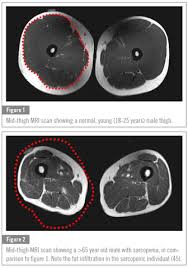

Sarcopenia Muscle Loss And Vitamin D Vitamindwiki

Sarcopenia Muscle Loss And Vitamin D Vitamindwiki from vitamindwiki.com